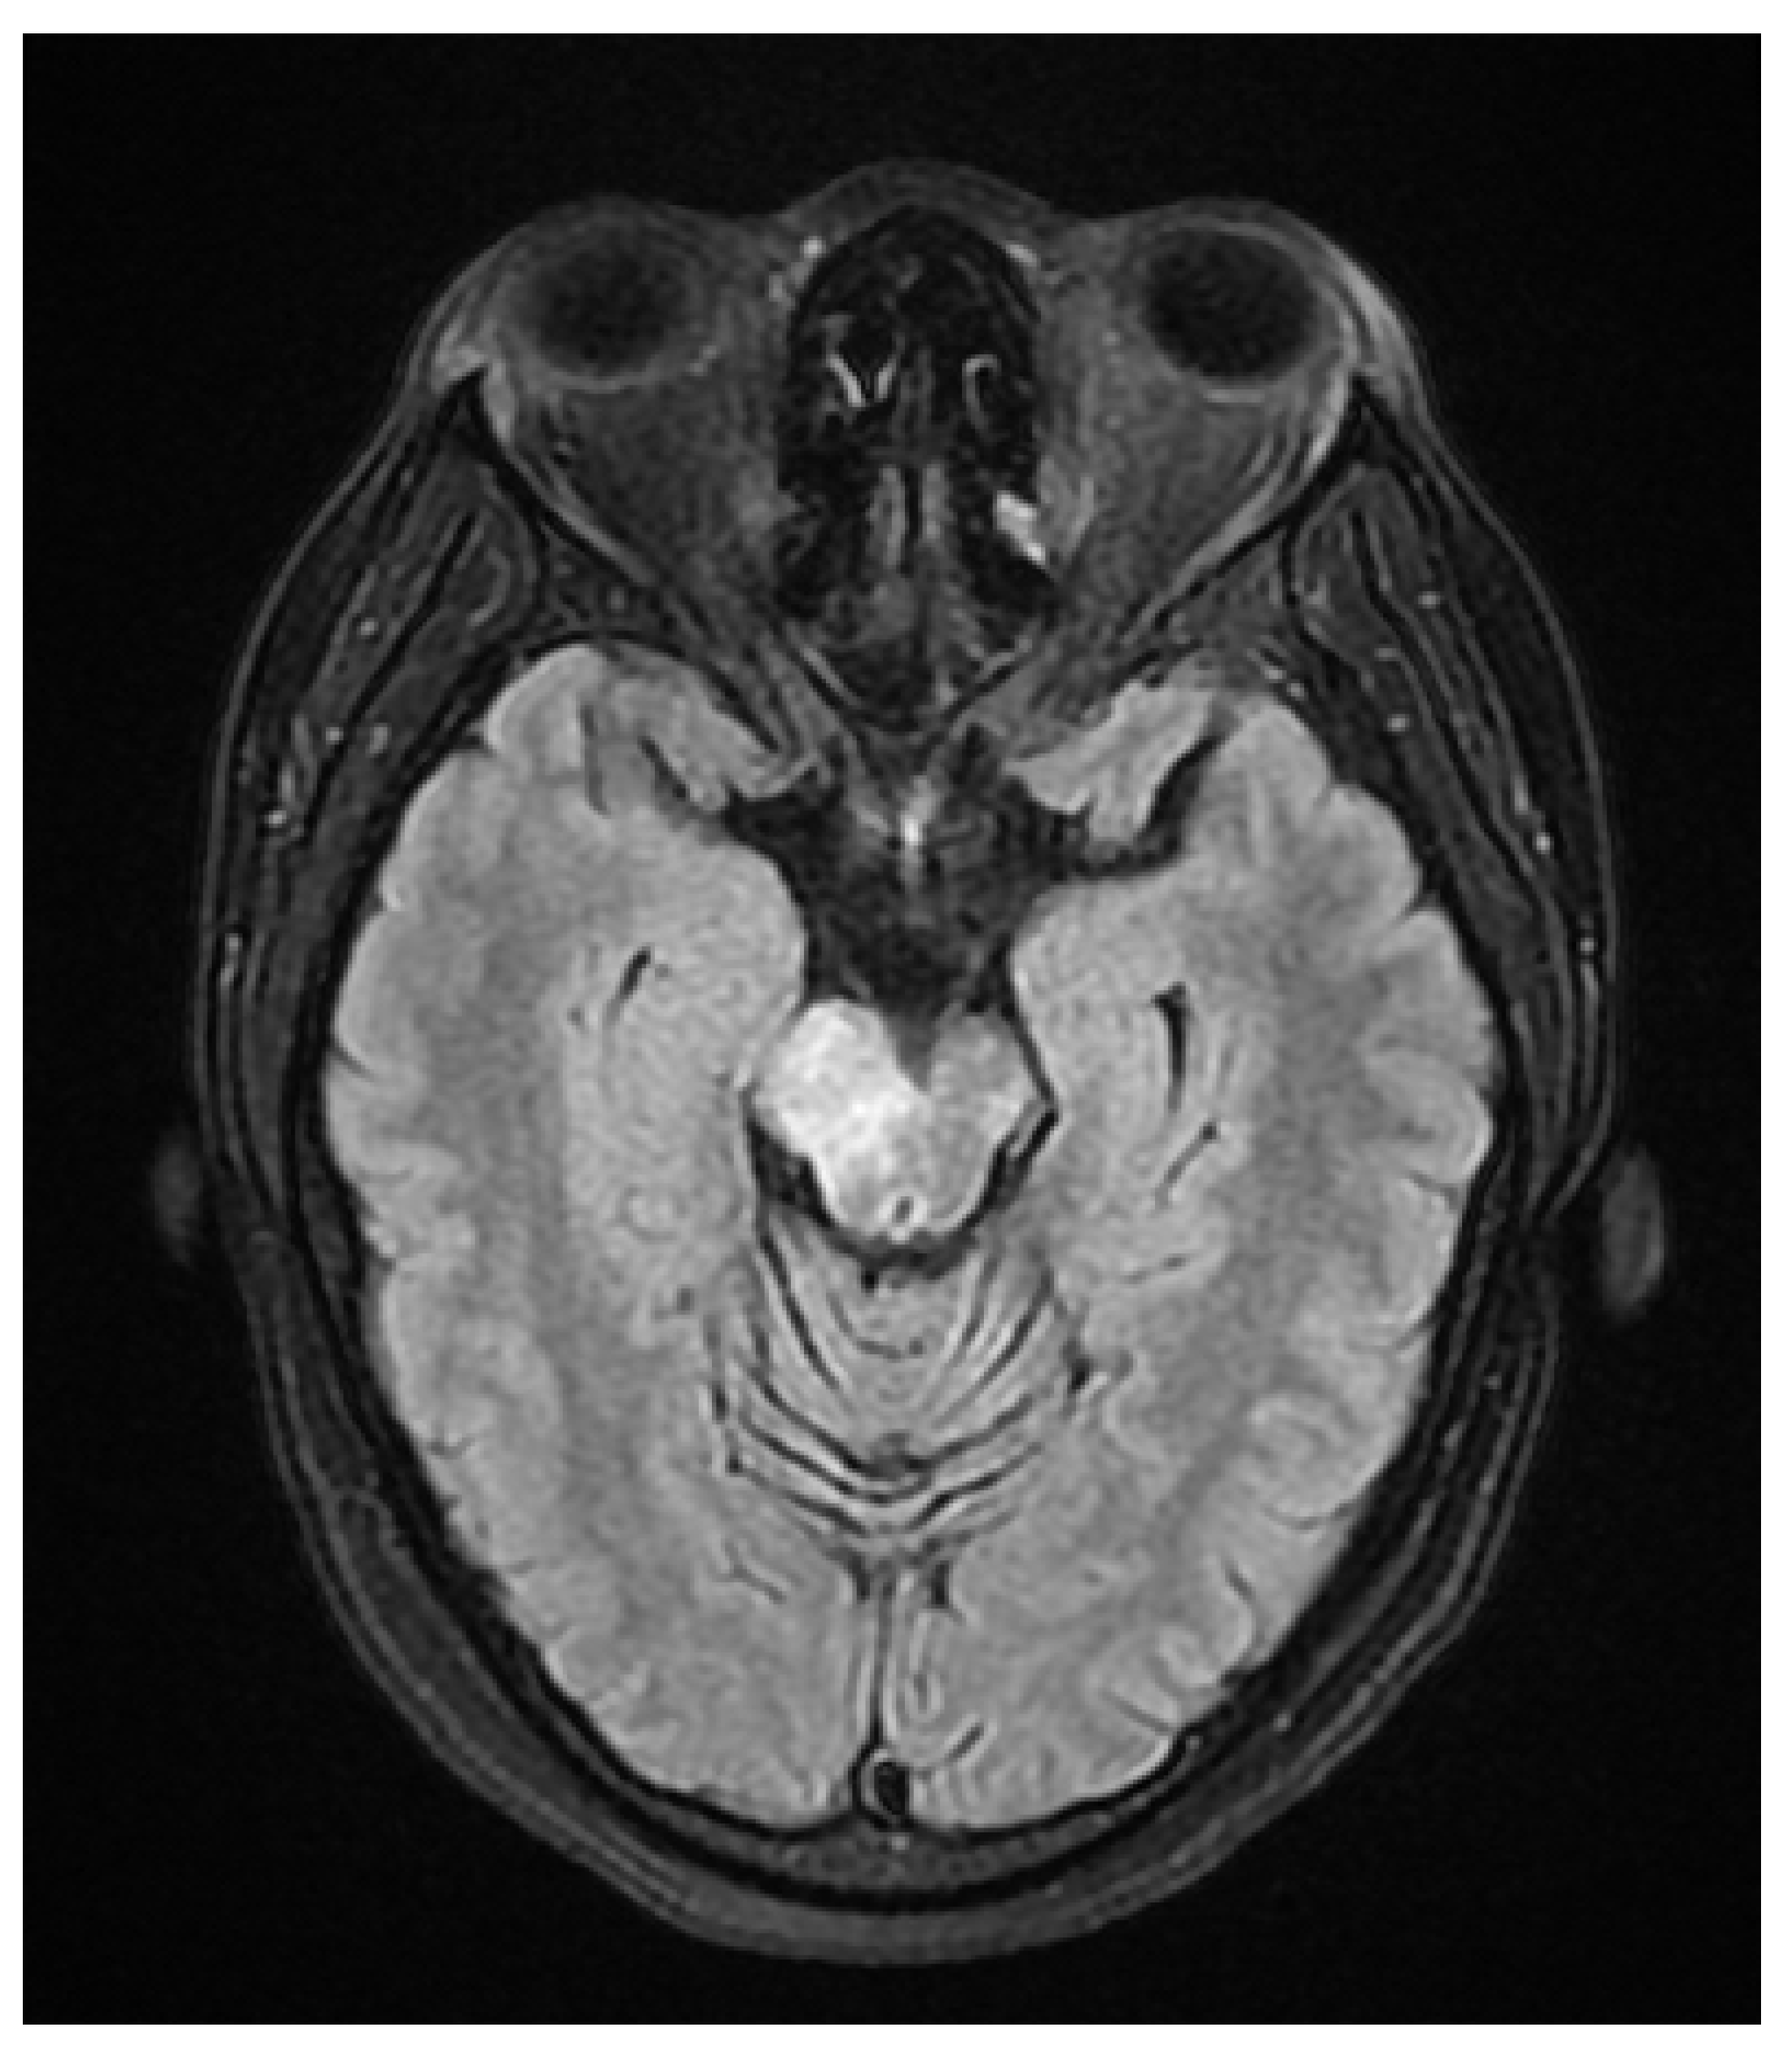

A 37 year old female presented to our hospital due to new onset severe headaches and right sided weakness with facial droop. The patient did not have any significant past medical history before this point. Patient was unable to speak properly and was found to have decreased responsiveness at bedside. Initial CT scan of the head without contrast revealed ill-defined edema involving the left periatrial white matter, involving the central gray matter and external limited internal capsule. MRI head with T2 Flair revealed diffuse edema and inflammation throughout the brainstem, pons, midbrain, and basal ganglia (Figure 1, Figure 2, Figure 3 and Figure 4). EEG showed diffuse slowing suggestive of moderate diffuse cerebral dysfunction without evidence of seizures or epileptiform activity. Lumbar puncture demonstrated a normal opening pressure, with CSF containing 2 red blood cells, 9 white blood cells of which 94% were lymphocytes, glucose of 58, and protein of 42. CSF bacterial cultures were negative, along with no evidence of active HSV or EBV infection. RPR was also negative. Pulse dose steroids were initiated in the ICU. Patient was slow to improve and was transferred to the neurological intensive care unit for further management. After 17 days in the ICU patient was discharged to a rehabilitation facility. Patient slowly improved with physical therapy but did continue to have some refractory lower extremity weakness. At the time of discharge, our patient was discharged on 20mg prednisone daily. Outpatient brain biopsy of the right frontal cortex revealed moderate gliosis but no abnormal lymphocytic infiltration. After thorough review of imaging findings and clinical presentation a diagnosis of acute disseminated encephalomyelitis was made by Neurology.

Figure 1. FLAIR Axial image white matter lesions in the internal capsule.